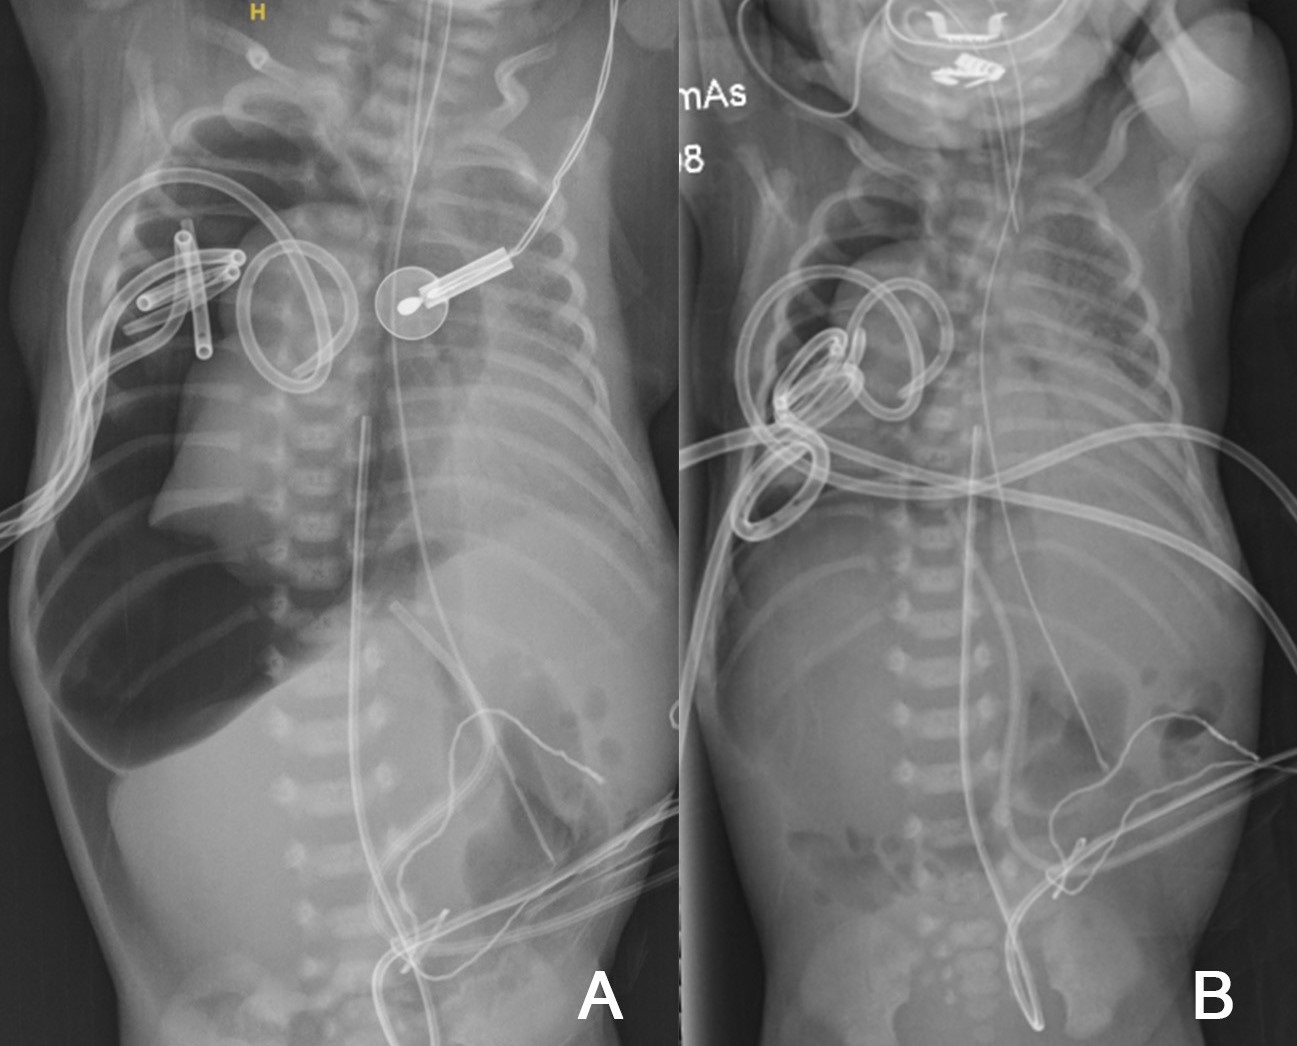

At 3 hours of age, due to sudden loss of chest movements and volumes on ventilation, the neonate was re-intubated. There was ongoing respiratory distress and CXR confirmed a right-sided tension pneumothorax (Fig. 1A). Needle aspiration followed by tube thoracocentesis (TT) with the underwater seal was undertaken (Fig. 1B) . The drain was placed on low-flow suction. One hour later, further desaturation and transillumination indicated a large residual pneumothorax, necessitating a second chest drain, also placed on low-flow suction. Ventilation improved and he remained on 25% FiO2.

An iatrogenic tracheobronchial injury was suspected. On day 2, he developed a greater oxygen requirement; transillumination and radiography confirmed persistent pneumothorax, this time with pneumomediastinum and pneumoperitoneum, requiring a third chest drain. He was then transferred to the regional pediatric center. After a fourth TT (Fig. 2B) due to a massive ongoing air leak (Fig. 2A), high-frequency oscillatory flow ventilation (HFOV) was tried.

Chest and abdominal radiographs showing right-sided pneumothorax (first diagnosis) – before (A) and after (B) drain 1.

Figure 2

Chest and abdominal radiographs showing right-sided pneumothorax, pneumomediastinum, and pneumoperitoneum (massive air leak)– before (A) and after (B) drain 4.